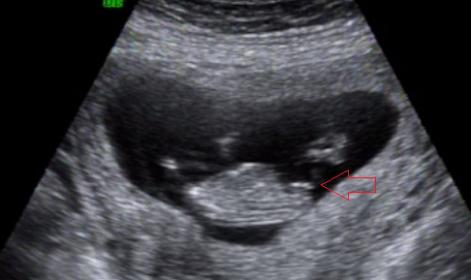

I am new to all this nub theory thing, and super curious on what we will have... any guesses? I have pointed what I think is the nub but not really sure I am right...

Yes you did correctly identify the nub, and Girl especially that last one thats a clean level fork

I'd guess girl , 12 weeks exactly? Or 12 weeks 3 days etc...